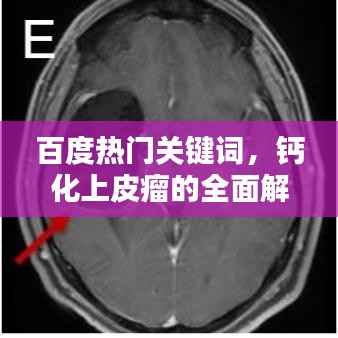

百度热门关键词,钙化上皮瘤的全面解析——从了解、诊断到治疗

当我们谈论“钙化上皮瘤”这一医学名词时,许多人可能会感到陌生和困惑,本文将通过“百度一下”的方式,带您全面了解钙化上皮瘤,包括其定义、成因、症状、诊断以及治疗方法。了解钙化上皮瘤钙化上皮瘤,也被称为皮肤钙化瘤,是一种...